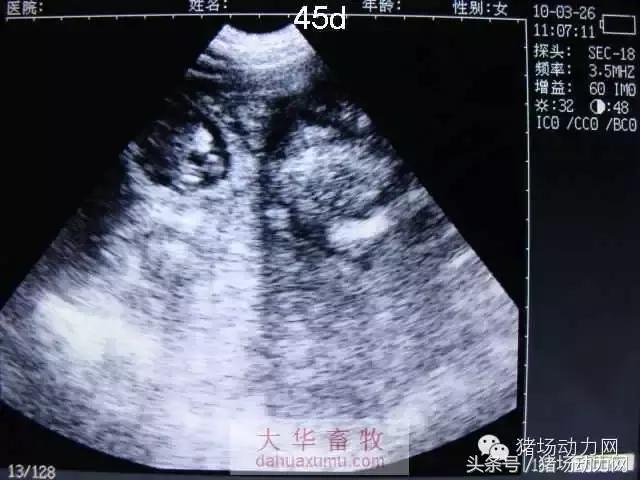

怀孕中期:41天——80天

以下为怀孕母猪21天到90天之内的变化图:

45天